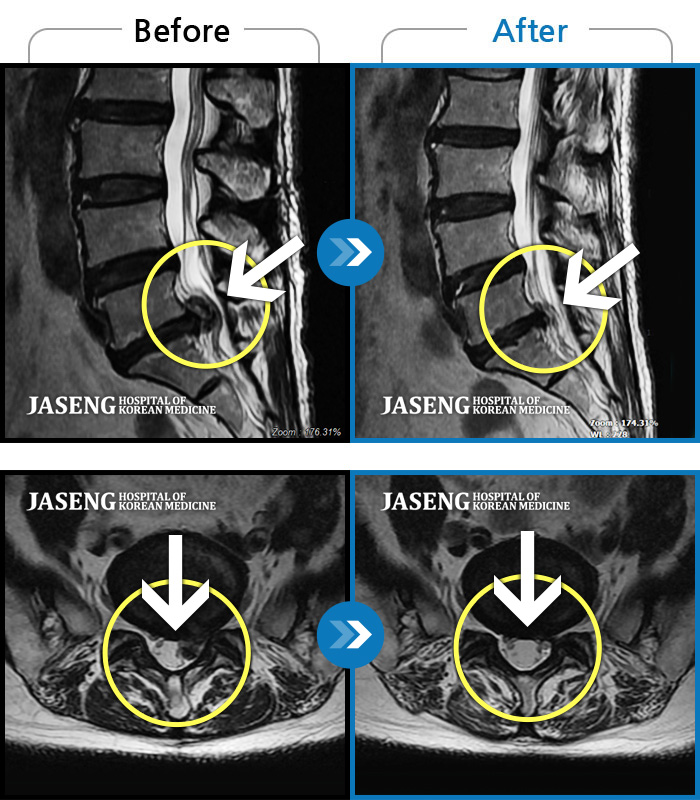

MRI ũ ʸ Ȯϼ.